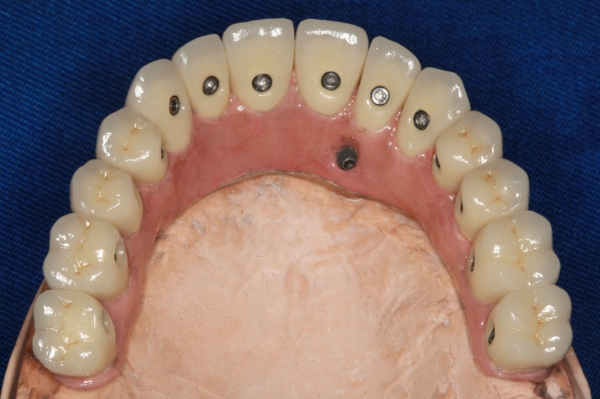

Prótese com dentes individuais no laboratório  - Clínica Cliniface

Prótese com dentes individuais no laboratório